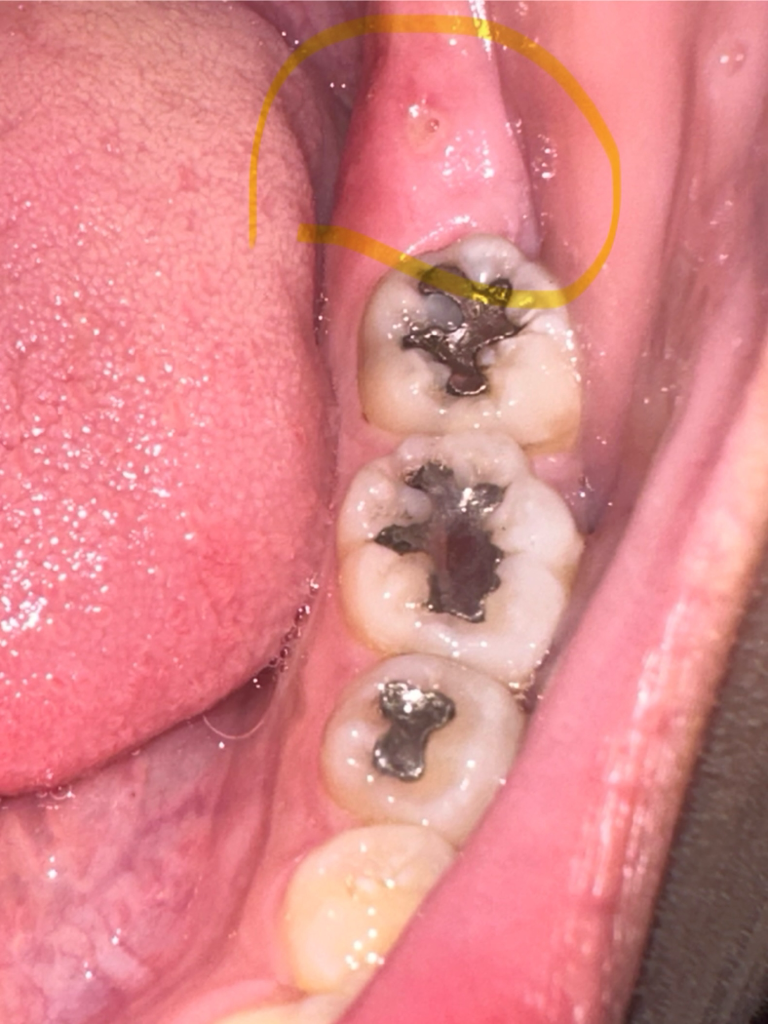

단순 구내염의 가능성도 있으나 말씀하신 것처럼 윗니가 아래 잇몸에 지속적으로 닿으면서 만든 외상성궤양의 가능성도 있습니다.

보통 단순 구내염은 별다른 처치를 하지 않아도 1~2주면 자연스럽게 회복되나 외상성궤양의 경우 원인요소를 제거해줘야 합니다.